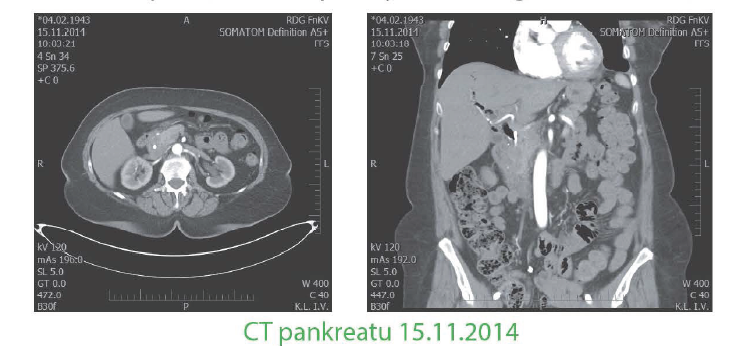

III. meta do pankreatu

- 8/2014 na CT při restagingu nově výrazná dilatace hepatocholedochu a intrahepatických žlučových cest bez jiného patol.nálezu, pacientka anikterická. Následně náhle vzniklý ikterus - ERCP se zavedením stentu. Doplněn UZ - susp.hypoechogenní ložisko hlavy pankreatu 28mm, nejspíše primární nádor. Nález potvrzen i na endosonu, FNAB bez nálezu maligních buněk. 26/11 /2014 pancreatoduodenectomia sec.Traverso- Longmire, pancreatico et hepatico et duodeno jejunoanastomosis, cholecystectomia. Histologicky- meta malig.melanomu, RO resekce, 1 O lymfatických uzlin negativních, 1 uzlina v oblasti v. cava inf. pozitivní, dále dispenzarizace